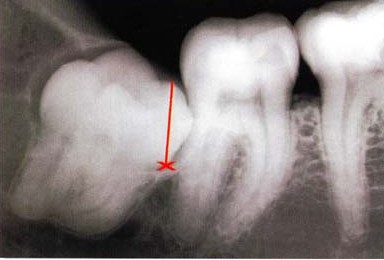

2、位置不正的智齿与第二磨牙之间容易积存食物残渣,而且不易清洁,一般数月可形成龋齿,直接破坏牙体组织。

5、邻牙及支持组织的吸收。阻生智齿可使下颌第二磨牙远中牙根完全吸收,而且阻生智齿与第二磨牙间常存在的慢性牙周炎也会造成牙槽骨的炎症性吸收。